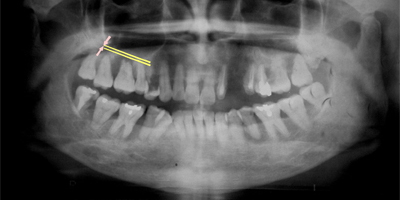

下記の写真をご覧ください(骨のない状態)。

骨がないため、骨が吸収し薄くなった状態がわかります。

サイナスリフト術により骨が増えた状態(ピンクの部分が骨が増えた状態)です。